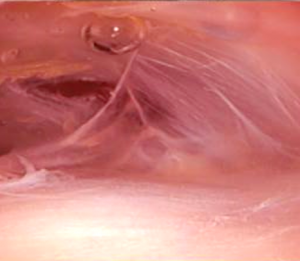

論文のタイトルは「Effectiveness of ultrasound-guided fascia hydrorelease on the coracohumeral ligament in patients with global limitation of the shoulder range of motion: a pilot study」で、烏口上腕靭帯に対するエコーガイド下ファシアハイドロリリースが肩の可動域にどのような効果を与えるかを検証した内容となっております。